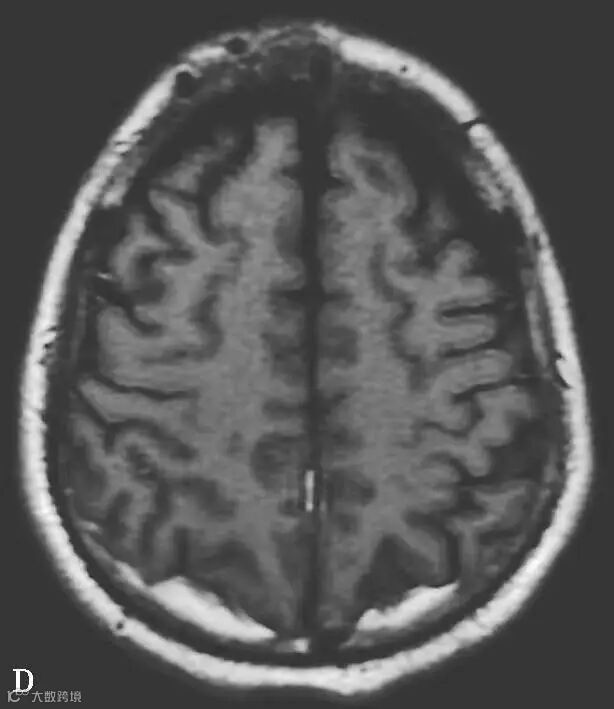

男,34岁,外伤后7天。A~H(A、B.T2WI,C、D.T1WI,E、F.T2WI-FLAIR,G、H.DWI):左侧岛叶及右侧顶叶白质可见斑片状稍长T1稍长T2信号,边缘不清,FLAIR及DWI呈高信号。双侧额部内板下可见新月形长T1长T2信号,FLAIR及DWI呈低信号。双侧顶枕部内板下可见弧形短T1长T2信号,FLAIR及DWI呈高信号

图6-11-2 弥漫性轴索损伤

男,36岁,外伤后2天。A~J(A、B.T2WI,C、D.T1WI,E、F.T2WI-FLAIR,G、H.DWI,I、J.ADC图):双侧额叶、半卵圆中心及胼胝体压部可见多发斑点状等T1稍长T2信号,边缘不清,FLAIR及DWI呈高信号,ADC图病灶信号减低 。